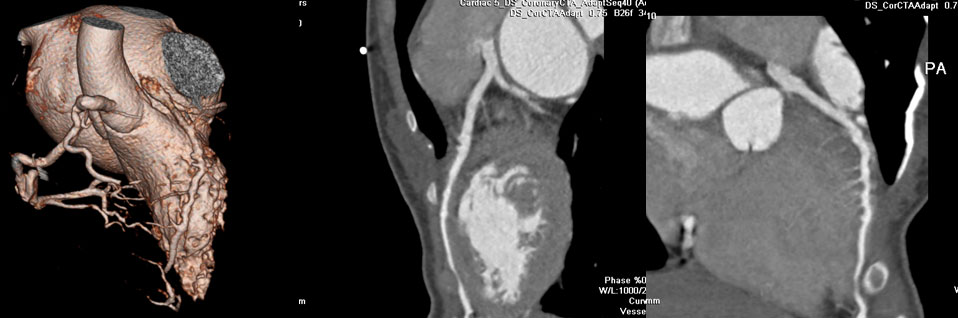

冠脉CTA

提示左侧冠脉走行于右室流出道和主动脉之间(图7 图8)。